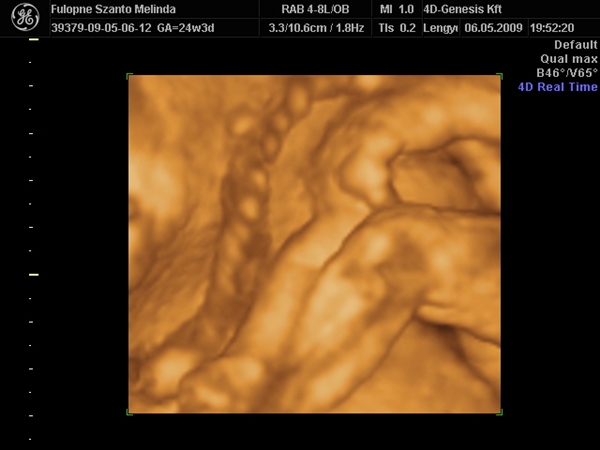

Na rakok képet,Budán voltunk a 4d genesis,de megmutatom,van honlapja.... Kép Kép Kép Kép Kép

Szóval!Nagyon csodálatos volt látni (nekem újra) a picúrt! :lol:

Mint ahogy kiderült,nem is olyan picúr!Ma vagyok 15 hét 2 napos,a bab méretei meg 16 hetesnek felel meg.Persze tudom,ez még változhat.Szegénykém olyan furi pózt vett fel,de hát ha neki úgy kényelmes,legyen úgy! :lol: :lol: :lol: :wink: Úgy képzeljétek el,mint a fordított C betű.Lent van a feje,felfelé áll a törzse és balra fordulva a lábai.Nem tudom elég érthető volt e így,de sajna jobban nem tudom elmagyarázni.

Átnézték a szívét( ok, meg van mind a 4üreg), a veséjét, az artériákat, vénákat, köldökzsinórt, megszámoltuk az ujjait. Kaptam képet is, 4D-set. Átkapcsolt 4Ds-re is.